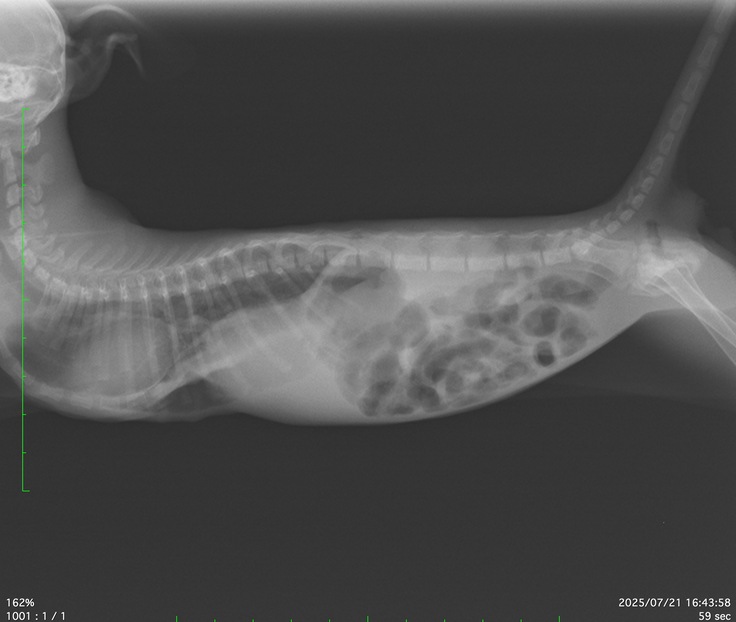

『漏斗胸』と診断され他の病院を紹介されました。

※『漏斗胸』とは猫の胸骨(胸の中央にある骨)が内側に凹んでしまう先天性の病気です。この凹みによって、心臓や肺が圧迫され、呼吸困難や循環器系の障害を引き起こすらしいです。

次の日紹介された病院へ行くと骨が肺を圧迫しているせいで肺が小さく変に空気を吸い込んでるのかガスが溜まってしまいお腹の中がガスでいっぱいで食欲も無くなっている。との事。改善するには手術をして骨を通常ある場所に戻すようです。

手術をしない場合はこの症状が続きガスが溜まり食欲を無くすのも繰り返す。

診察をし、そのまま(7/21)入院になり7/23に手術、7/28に退院いたしました。

病院面会 手術の内容を写真などで説明していただきました。

曲がった骨をお腹に巻いたギブスのようなものに縛り通常骨がある位置へ固定させたようでレントゲン写真を見ると21日のレントゲンとは全く違いました。

しかしいいことばかりでは無く心臓の数値が高い事、肺が白くなってしまっている事など心配事もあることを伝えられました。

2025年7月21日に入院し、7月23日に1回目の手術を行いました。

7月28日に経過が良く退院。

過去(2025/07/23)の手術費:税込み22万円

2025年7月23日に手術

2025年7月28月に退院